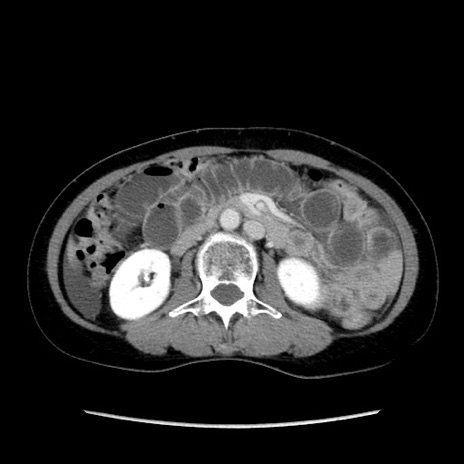

症例32(横断像)

【症例】40歳代 女性

【主訴】上腹部痛、嘔気・嘔吐

【現病歴】約9時間前頃から急に上腹部痛、嘔気、嘔吐が出現。改善しないため救急要請。

【既往歴】子宮頚癌(広汎子宮全摘術、放射線療法)、腸閉塞

【身体所見】腹部:平坦、軟、腸雑音亢進、上腹部を中心に腹部全体に圧痛あり。

【データ】WBC 8400、CRP 0.03